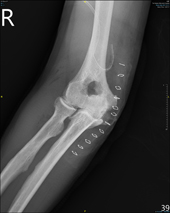

主要用來治療輕度到中度肘關節炎,同時此術式結合肘關節鏡的方式治療(如;圖二),只需要兩個小傷口就可達到切除骨刺、移除碎骨等,且有減輕疼痛的效果。只是相對於嚴重的肘關節炎來說,單用此術式就很難有效增進關節活動程度,所以必須以開放性Outerbridge-Kashiwagi術式治療(如:圖三),就可達到較佳的關節活動度。

本院最近發表開放性和關節鏡下Outerbridge-Kashiwagi肱尺肘關節成型術手術。其中開放性手術的病患症狀都是因為肘關節彎曲伸直活動產生疼痛、關節活動度減少,經由此開放性術式治療後,其關節活動度都有明顯增加。而在關節鏡手術族群中,對於選擇適應症較為嚴謹,適合的對象為輕度到中度的肘關節炎,病患症狀也多是在活動時疼痛,經由關節鏡手術治療後,關節活動度也都有明顯改善,且相對於開放性手術傷口較小,術後恢復也比較快。所以對於肘關節炎的治療,醫師都會依據各病患狀況,實行合適的術式。

圖三、Outerbridge-Kashiwagi手術術後X光片